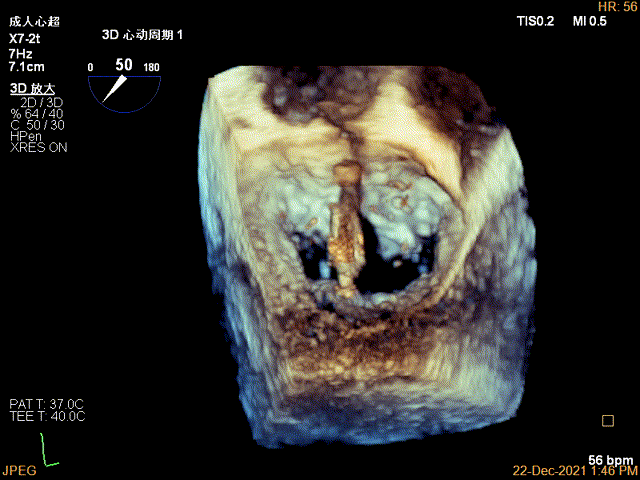

3D MV View:P2区脱垂

TEE Bicom view:二尖瓣后叶P2区大范围脱垂,部分累及1区及3区